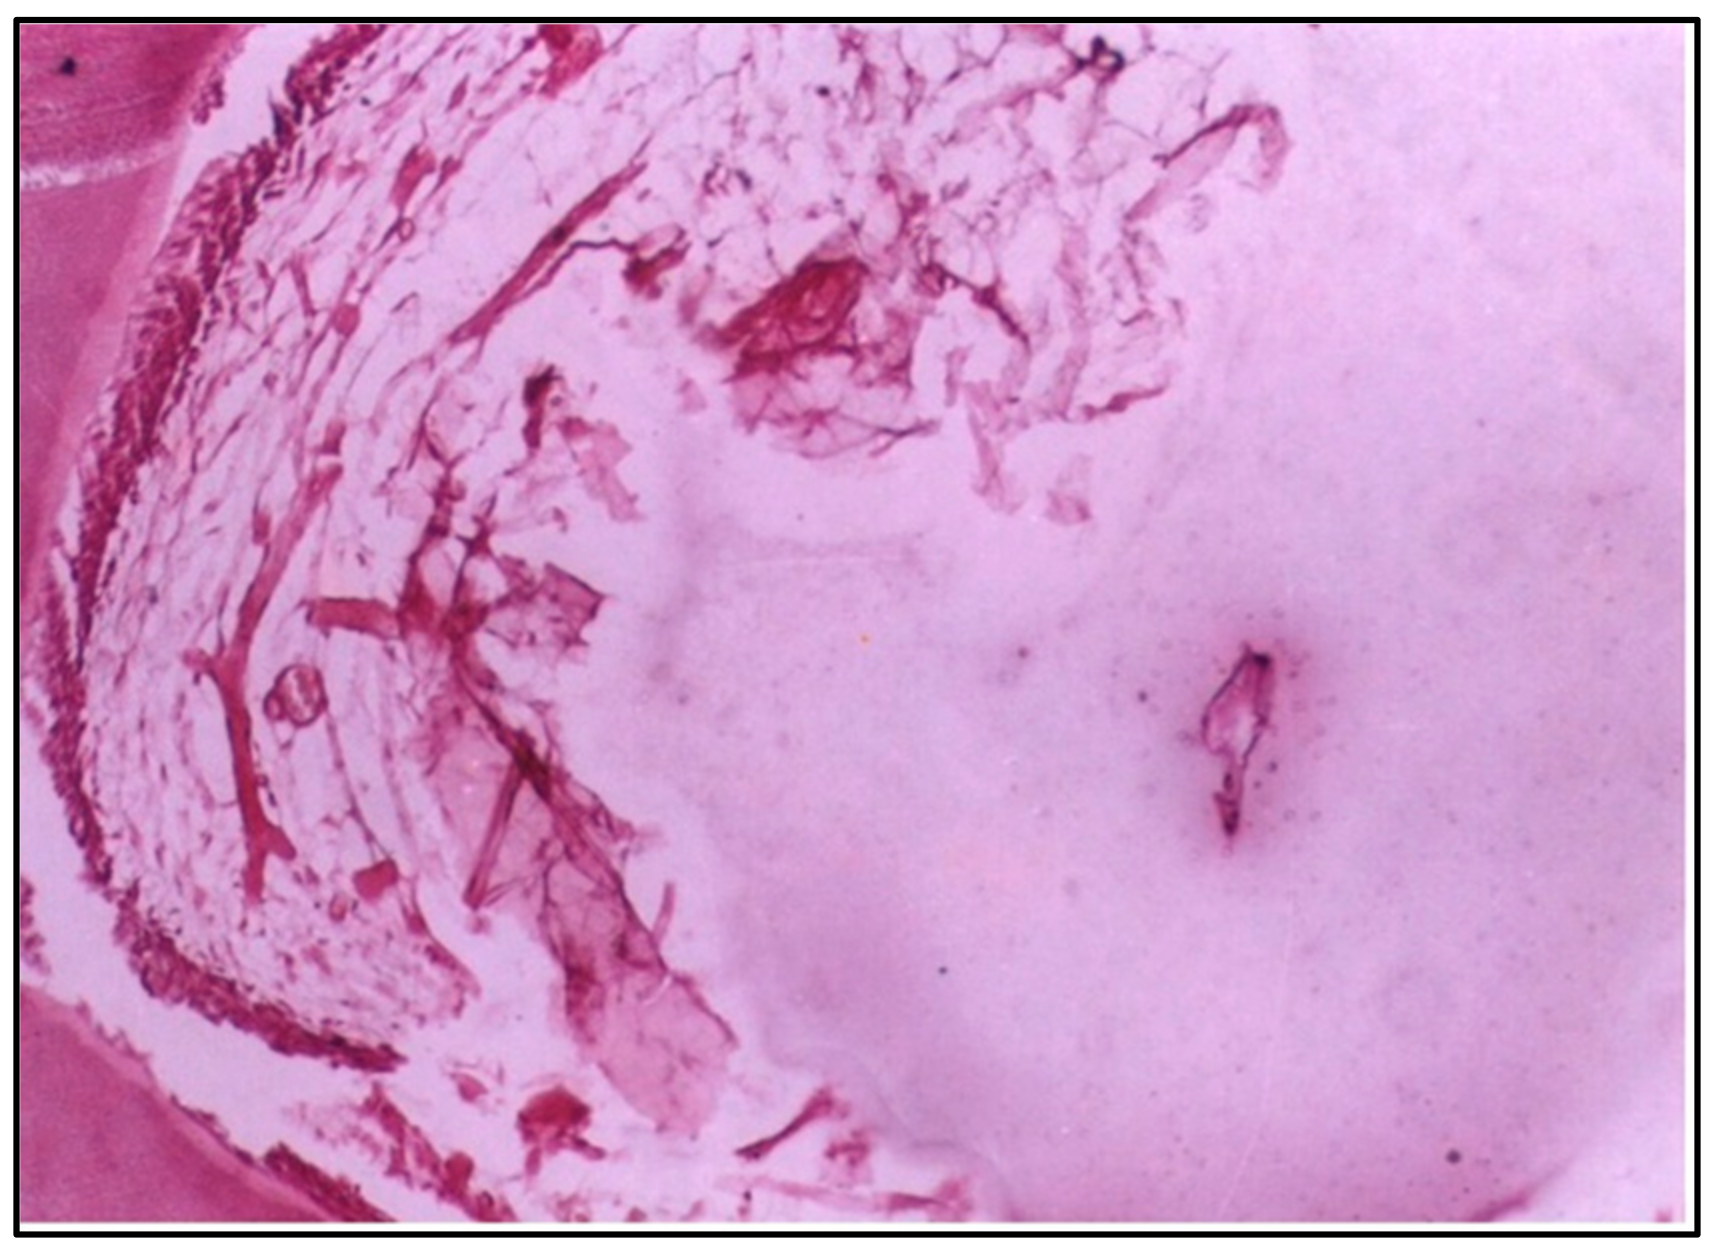

At 2 weeks, the pulp tissue displayed moderate disorganization, but the pattern of damage was more localized compared with Group I. The cells and fibers at one side of the tissue were condensed, which could indicate fibrosis, a common reaction to injury. Meanwhile, the central area was more loosely arranged, reflecting ongoing inflammation (Figure 3). Notably, one of the specimens had a microabscess formation, signifying localized pus accumulation due to infection or significant inflammation, which was more severe than the vascular changes observed in Group I (Figure 4).

Concerning the conventional composite resin, the specimens showed moderate disorganization of the pulp tissue at 2 weeks, with one specimen presenting microabscess formation, indicating localized areas of necrosis and acute inflammation. This aligns with previous studies highlighting the cytotoxic potential of certain composite resins, often attributed to their chemical constituents, such as Bis–GMA and TEGDMA [10].

Figure 4. LS of the pulp (Group II, 2 weeks) showing a generalized appearance of disorganization with microabscess formation (H & E Stain, ×100).